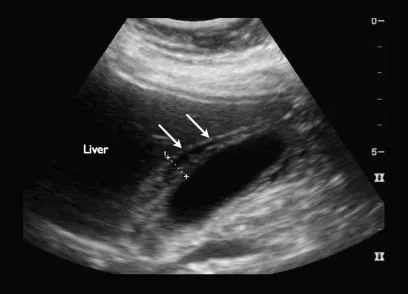

- Dx: USG (CBD >6mm), MRCP, EUS.